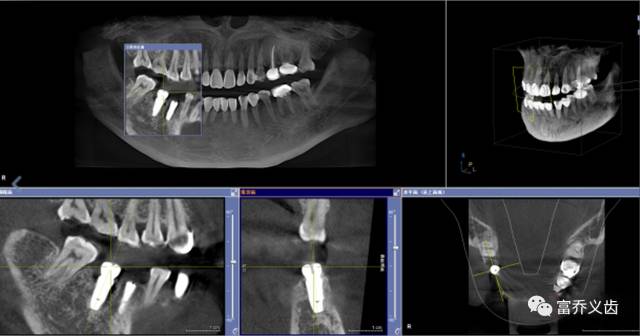

手术后CBCT以及曲面断层片